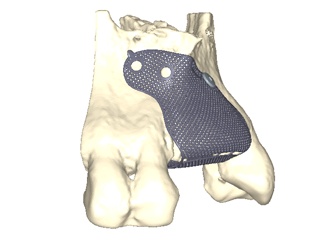

Yngre kvinne som mistet tenner 11-22 gjennom traume. Både en horisontal og vertikal defekt i et estetisk utfordrende område. En Yxoss 3D-printet membran produseres gjennom planleggingsverktøyet, i dette tilfellet IO-skanning og CBCT som grunnlag. En preprotetisk voksing på den tiltenkte suprakonstruksjonen produseres for å forutsi fremtidig protese og tiltenkt beinvolum. Partikulært bein påføres membranen som deretter fikseres på plass. Etter 6 måneders helbredelse fjernes membranen. Regenerert bein uten pseudoperiosteum er påvist, implantater kan plasseres med gode marginer og god protesetilstand.

Planlegging av Yxoss membran

Yxoss membran fylt med partikkelformet autologt bein og Geistlich Bio-Oss.